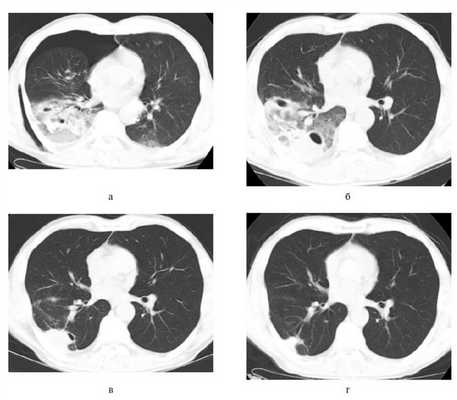

Разрывы легкого с образованием полостей в толще ткани в сочетании с очагами ушиба на основании данных СКТ были верифицированы у 97 пациентов (рис. 2, а), Рисунок 2. Спиральные компьютерные томограммы пациента после закрытой травмы груди. а — 1-е сутки: коллабирование правого легкого на 1 /3 объема за счет пневмоторакса. В проекции VII—X сегментов правого легкого и X сегмента левого легкого определяются зоны ушибов, на этом фоне контуры гематомы нечеткие, что затрудняет оценку ее объема. В нижней доле правого легкого определяются включения газа; б — 9-е сутки: обратное развитие ушиба левого легкого; объем и интенсивность ушиба правого легкого уменьшились, визуализируется гематома объемом 103 см 3 с наличием включений газа объемом 31 см 3 , по ходу междолевой плевры единичное включение газа 5 см 3 ; в — 29-е сутки: положительная динамика в виде уменьшения объема травматической полости до 60 см 3 и обратного развития ушиба нижней доли правого легкого; вокруг полости и в прилежащей междолевой плевре определяются участки пневмофиброза; г — 3,5 мес: обратное развитие травматической полости с формированием субплевральн однако в большинстве этих наблюдений имелись трудности в определении точных размеров и объема гематомы легкого из-за коллабирования или наличия массивного ушиба ткани легкого. По этой же причине не были диагностированы разрывы крупных бронхов, имевшие место у 3 пострадавших с легочными кровоизлияниями. Истинные гематомы легкого без включений газа при первичном исследовании определялись у 23 пациентов, объем их составил от 3,5 до 194 см 3 (в среднем 49,2±16,5 см 3 ). У 57 пострадавших структура гематомы при первичном исследовании была неоднородной за счет включений плотности газа, у 17 пациентов полость в легком содержала только газ. Диаметр газосодержащих полостей в легком колебался от 3 до 116 мм (в среднем 41,9±12,3 мм), объем от 3 до 370 см 3 . В 16 из 97 наблюдений определялись множественные полости в легком, в том числе в 12 - односторонние, в 4 - двусторонние.